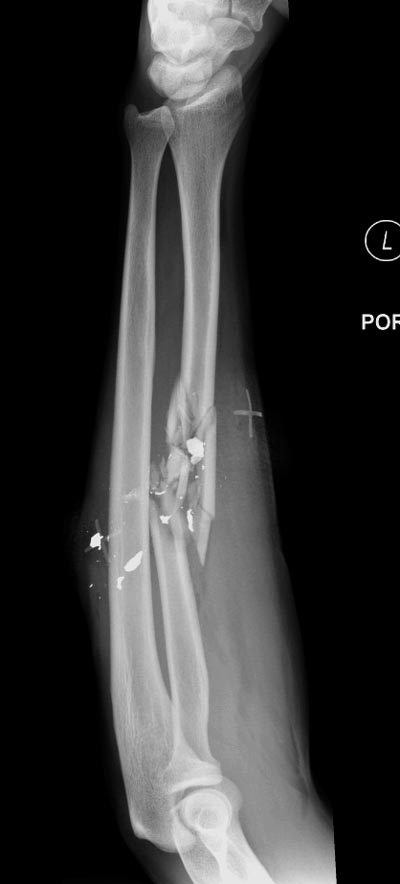

Здесь примеры: двоюродные братья с ранением предплечья, у одного

локтевая, а у второго лучевая. В следующее утро локтевая фиксирована без

обнажения фокуса травмы из небольших доступов, а второй из обычного

волярного доступа. А клинический снимок из прошлых операций...